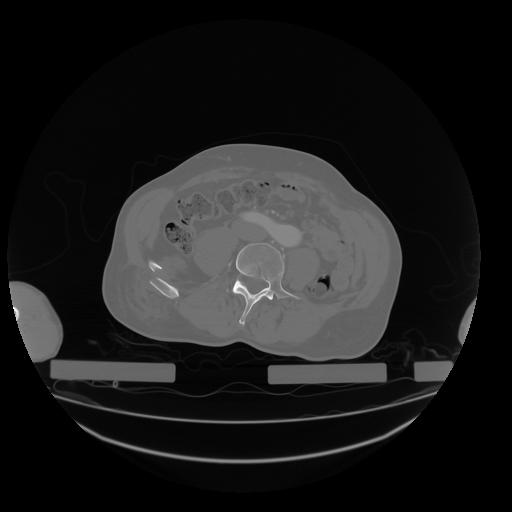

28 CUERPO,CE,Vol,2.0,CUERPO,,